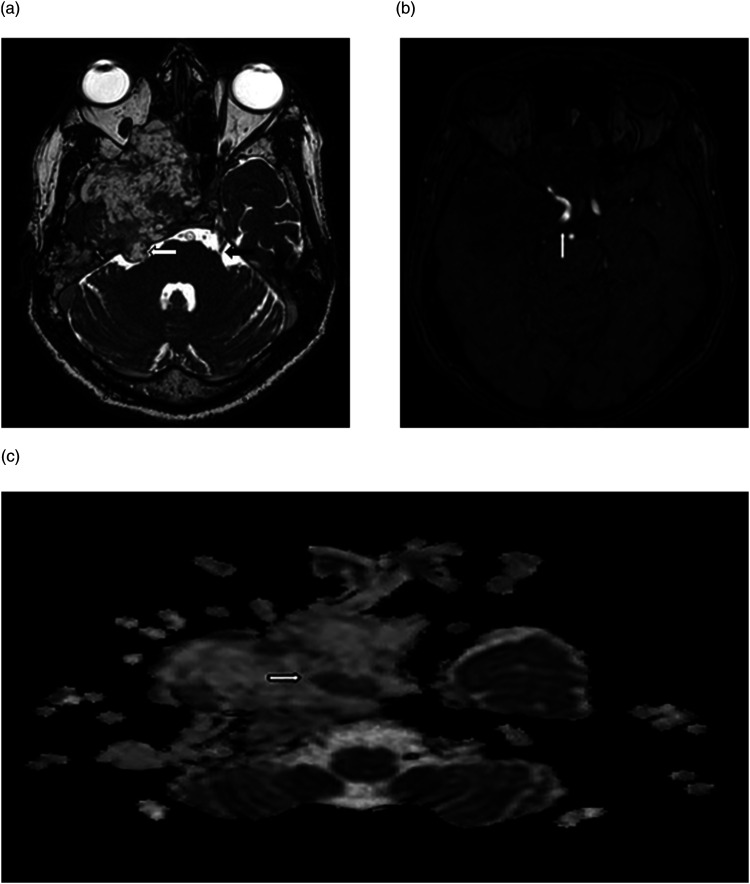

神经节血管瘤是一种罕见的肿瘤,由腹膜后和纵隔后交感神经引起。颅内三叉神经节瘤更为罕见,迄今仅有七例报道。我们报告了一例 65 岁男性的病例,他患有右侧搏动性头痛,右眼失明。磁共振成像显示,中颅窝有一个界限不清的肿块病变,少数区域的表观弥散系数降低,并有多处微出血。通过翼下和颞下入路进行右侧中开颅手术,对肿瘤进行了碎块剥离。检测到的组织学特征与三叉神经节瘤(成熟型)相符。

Ganglioneuromas are rare tumors arising from retroperitoneal and posterior mediastinal sympathetic nerves. Intracranial trigeminal nerve ganglioneuromas are even more rare, with only seven cases reported to date. We present a case of a 65-year-old male with a right-sided throbbing headache type and blindness in his right eye. Magnetic resonance imaging revealed an ill-defined mass lesion in the middle-cranial fossa, with a few areas having a reduced apparent diffusion coefficient and multiple microhemorrhages. Piecemeal debulking of the tumor was achieved by performing a right-middle craniotomy via the pterionic and sub-temporal approach. The detected histological features matched those of a ganglioneuroma (maturing type) of the trigeminal nerve.